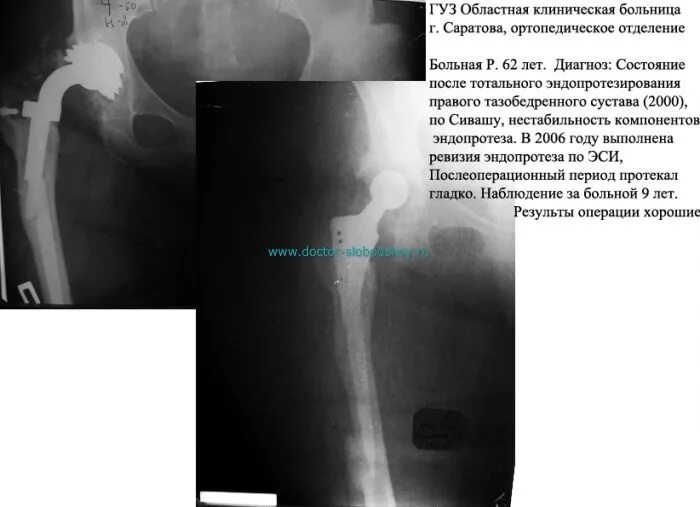

Ревизия тазобедренного сустава